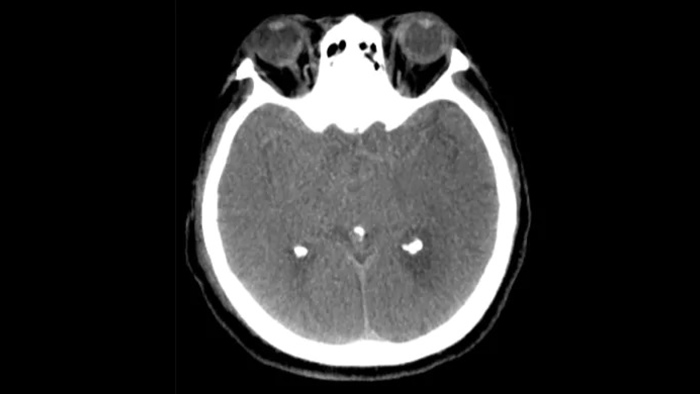

SmartCT Soft Tissue  genera una visualización de los tejidos blandos similar a la de una TC y apoya el diagnóstico del accidente cerebrovascular de tres maneras. Una exploración sin contraste ayuda a detectar los cambios isquémicos tempranos. Una exploración de fase temprana ayuda a identificar la oclusión proximal. Una exploración con contraste de fase tardía ayuda a detectar colaterales.